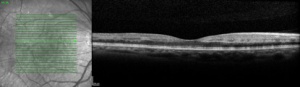

It is characterized by hyperreflective band-like, multiple, or isolated focal or diffuse lesions visible at the level of the inner nuclear layer (INL) in patients presenting with acute onset of negative scotoma. It is descriptively termed PAMM due to parafoveal position of the causative grey lesions with near-infrared reflectance imaging, and the SD-OCT localization of involvement to the middle layer (INL) of the retina.

On OCT, the acute lesions of PAMM characteristically appear as placoid, hyperreflective bands at the level of the INL, sparing the outer retina, showing corresponding hypoautofluorescence on fundus autofluorescence and are hyporeflective and well-demarcated on near infrared reflectance. A legacy of thinning and atrophy of the affected INL ensues. It is responsible for the permanent visual deficits that patients with PAMM typically experience.